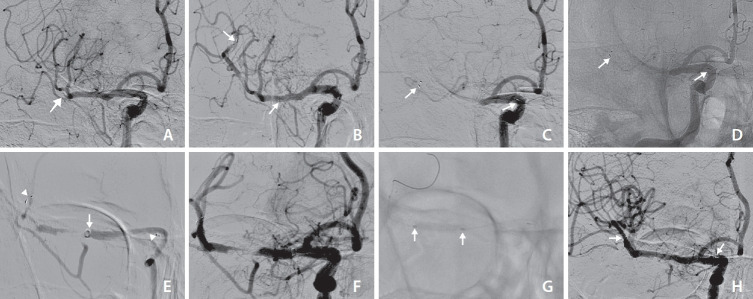

Mechanical thrombectomy using a stent retriever is a widely-used technique for recanalizing occluded cerebral arteries in acute ischemic stroke. Although rare, inadvertent stent detachment has primarily been reported with earlier stent retriever designs. We present 2 cases of inadvertent stent detachment with the pRESET stent. In the first case, an elderly patient presented with right middle cerebral artery occlusion and experienced stent detachment during the second retrieval. Despite this, successful recanalization was achieved through balloon angioplasty. In the second case, an elderly patient experienced stent detachment after the third retrieval, and recanalization of the M1 segment was unsuccessful due to the inability to pass the microcatheter. The first patient had a modified Rankin scale (mRS) score of 3, while the second had a poor prognosis with an mRS score of 5. These cases highlight that inadvertent stent detachment can impact outcomes, and balloon angioplasty may serve as a useful salvage therapy.